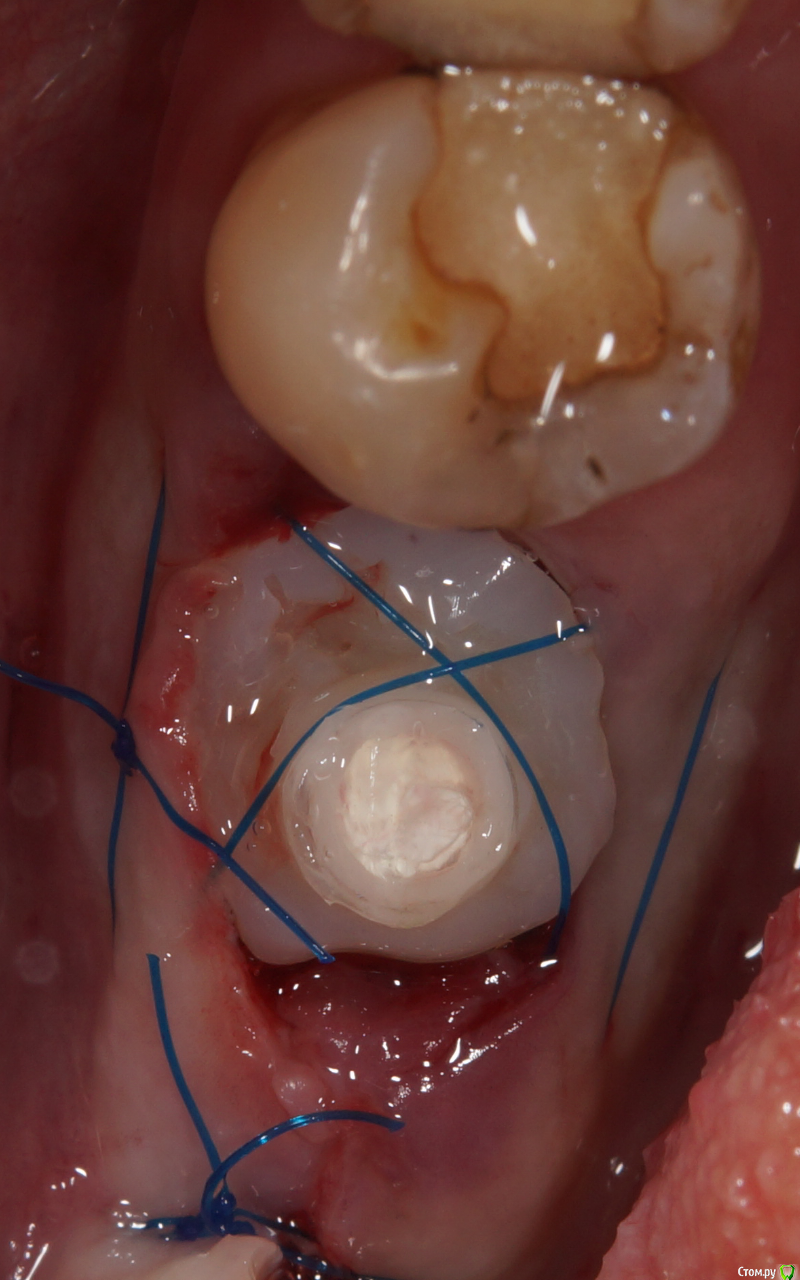

Irouil Опубликовано 23 сентября, 2017 Поделиться Опубликовано 23 сентября, 2017 Вот собственно моя проба пера. Дистально вышел провалище потому как не знал вообще как туда лапку нарастить хны хны А все остальное заняло минут 40, наверное. Долго, сст быстрее выходит забрать. Ссылка на комментарий